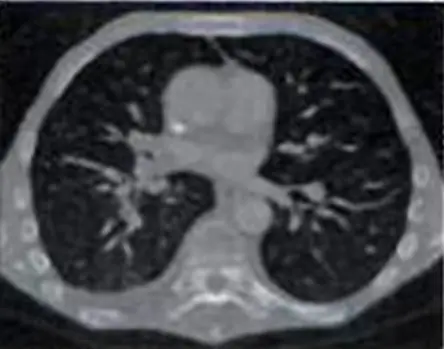

觀察題目提供的胸部軸狀切面(Axial CT)影像,我們可發現以下幾個關鍵特徵:

- 肺野(Lung fields):肺部背景呈現純黑色,並無法觀察到呈現灰色的肺實質(parenchyma)細節,只能看見呈現深灰色的肺血管分支。

- 軟組織(Soft tissues):心臟與胸壁肌肉的影像亮度偏暗,呈現深灰色。